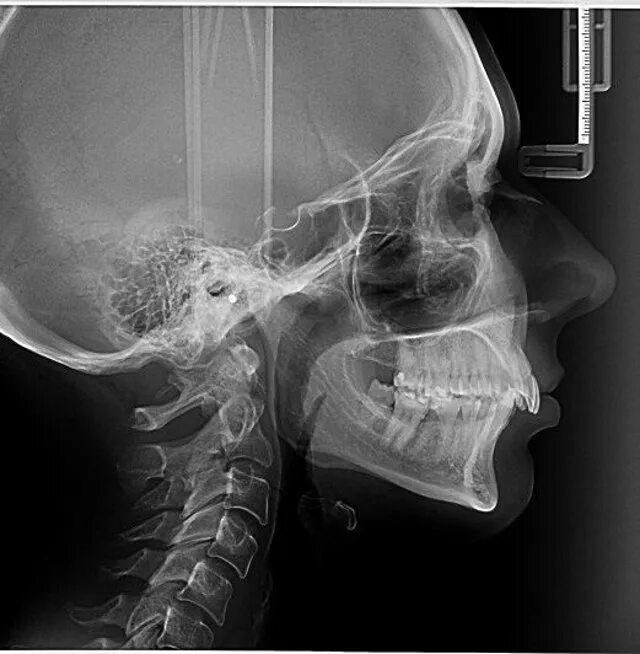

Source x rays